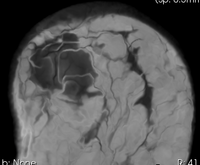

this is the fixed reference image: PreRx Breast MRI with large tumor mass lleft this is the moving image, to be registered with the reference above: PostRx Breast MRI with tumor largely absent

moving image

post Rx MRI